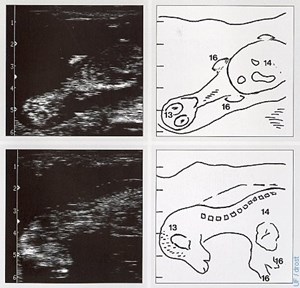

Bovine fetus, ultra…